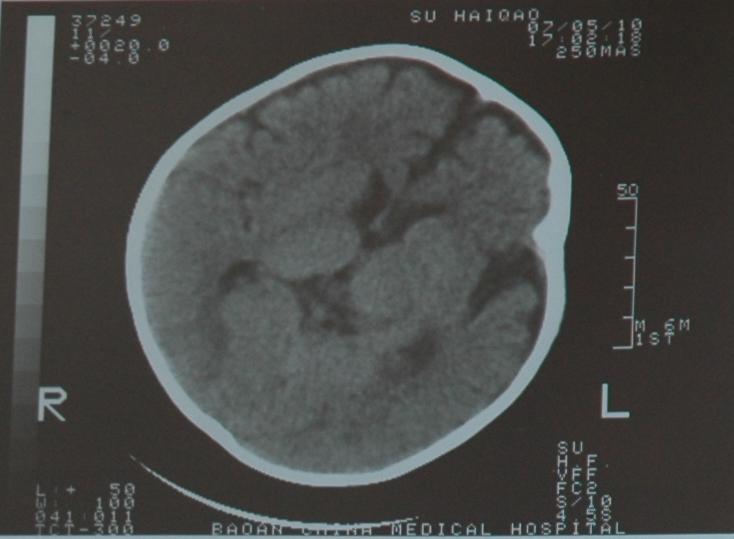

检查部位:头颅ct扫描

层厚:10mm     层距:10mm

扫描所见:双侧额颞部颅骨内板下方见对称性带状脑脊液样低密度影,并向前纵裂延伸,两侧大脑半球、脑干及小脑实质密度未见异常,侧脑室及三脑室略宽,双侧额叶脑沟深深加宽。四脑室形态无变形、移位或扩张,中线结构居中。

ct诊断:1、外部性脑积水(少量)。2、侧脑室、三脑室略宽,双侧额叶脑沟增深加宽,请结合临床。